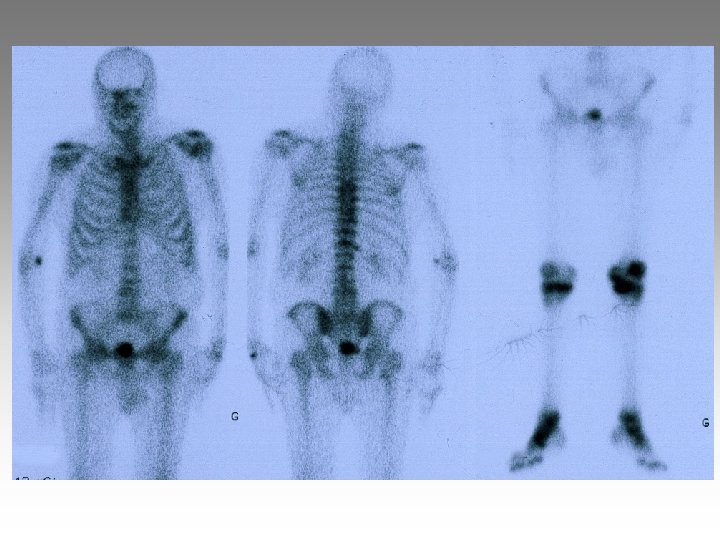

Hanche, T. , fract. fatigue Tendinites bursites, radic. Genou douloureux non traumatique Sémiologie Ponction +++ mécanique inflammatoire Rx inflammation Rx N Rx a. N < 40 ans interligne pincé Arthrose FT - FP contexte +++ > 40 ans Biologie, BS, Rx, IRM, écho interligne normal IRM AND, FF Paget, HOV ONA, OAN OAPH Ostéochond. infection IRM Arthroscopie Scinti. Os. LC Ménisque Coagul. PR, RP, Still, LED, SA…. Goutte, CCA AND ONA Ostéochondrite Pyogène, BK, Gono. , autres Hydarthrose X? Ostéochondromatose Synonite VN, T. , coag.

Genou douloureux non traumatique Sémiologie Ponction +++ mécanique inflammatoire Rx inflammation Rx N Rx a. N < 40 ans interligne pincé Arthrose FT - FP contexte +++ > 40 ans Biologie, BS, Rx, IRM, écho interligne normal IRM AND, FF Paget, HOV ONA, OAN OAPH Ostéochond. infection IRM Arthroscopie Scinti. Os. LC Ménisque Coagul. PR, RP, Still, LED, SA…. Goutte, CCA AND ONA Ostéochondrite Pyogène, BK, Gono. , autres Hydarthrose X? Ostéochondromatose Synonite VN, T. , coag.

Genou douloureux non traumatique Sémiologie Ponction +++ mécanique inflammatoire Rx inflammation Rx N Rx a. N < 40 ans interligne pincé Arthrose FT - FP contexte +++ > 40 ans interligne normal IRM AND, FF Paget, HOV ONA, OAN OAPH infection Biologie, BS, Rx, IRM, écho IRM Arthroscopie Scinti. Os. LC Ménisque Coagul. PR, RP, Still, LED, SA…. Goutte, CCA AND ONA Banal, BK, Gono. , autres Hydarthrose X? Ostéochondromatose Synonite VN, T. osseuse